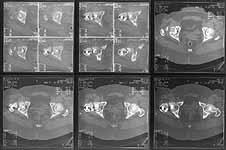

A subtrochanteric osteotomy was performed (a bit distally), after compression the lower crew was replaced with 3 monocortical. Then retrograde reaming was performed and UFN 12 mm was inserted and locked statically (with proximal screw through the plate). The neck gap looks well compressed. Image attached. Comments are welcome.

The valgus osteotomy has improved the position of the femoral neck fracture

The blade plate is in the anterior and proximal aspect of the femoral head

What activity level is planned? Keep a close eye on the femoral head and neck. They will determine outcome, primarily.